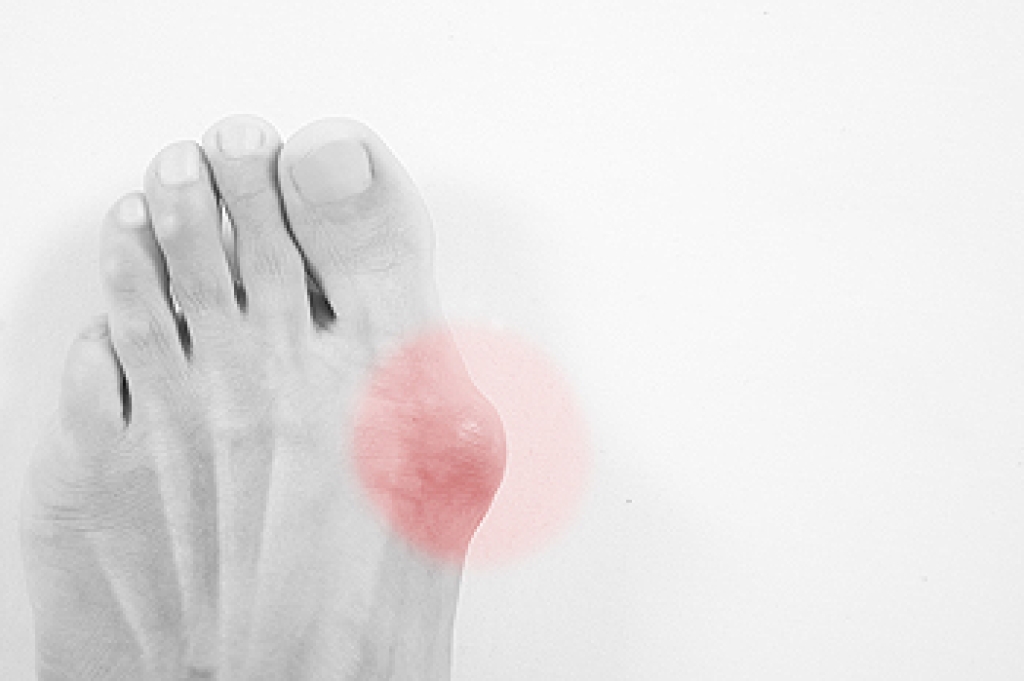

A bunion is a bony bump that forms at the base of the big toe when the joint becomes misaligned. It often appears as a swollen, red, and painful lump that can make walking difficult. Bunions develop due to genetics, wearing tight shoes, or foot structure issues. Risk factors include a family history of bunions, arthritis, and wearing ill-fitting footwear. A podiatrist can evaluate the severity of the bunion, provide pain relief options, recommend proper footwear, and discuss surgical correction, if needed. If you have signs of a bunion developing, it is suggested that you consult a podiatrist who can guide you on relief and management tips.

Bunions are painful bony bumps that usually develop on the inside of the foot at the joint of the big toe. As the deformity increases over time, it may become painful to walk and wear shoes. Women are more likely to exacerbate existing bunions since they often wear tight, narrow shoes that shift their toes together. Bunion pain can be relieved by wearing wider shoes with enough room for the toes.

- Redness and inflammation

- Pain and tenderness

- Callus or corns on the bump

- Restricted motion in the big toe